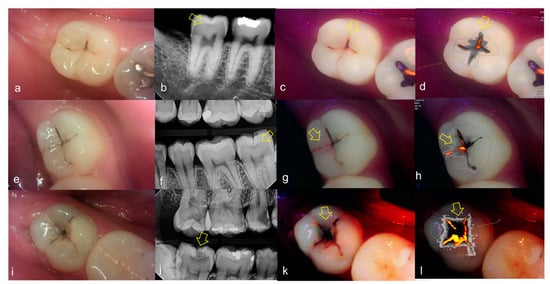

Figure 5.

Occlusal dental caries: (a–d) QLF caries score 2 (fluorescence loss and red fluorescence glow extending around pits and fissures) and radiographic caries score 3 (radiolucency extending to the middle 1/3 of the dentine) on #47; (e–h) QLF caries score 3 (red fluorescence glow extending around pits and fissures and a dark shadow from dentin present) and radiographic caries score 3 (radiolucency extending to the middle 1/3 of the dentine) on #37; (i–l) QLF caries score 3 (red fluorescence glow extending around pits and fissures and a dark shadow from dentin present) and radiographic caries score 3 (radiolucency extending to the middle 1/3 of the dentine) on #47; (a,e,i): white-light image of QLF; (b,f,j): fluorescence image of QLF; (c,g,k): bitewing radiograph; (d,h,l): analyzed QLF image using QA2 software.

3.2. Proximal Dental Caries

Evaluating proximal dental caries according to the QLF criteria and X-ray criteria, moderate positive correlation was observed (r = 0.63, p < 0.0001). Among the QLF parameters classified based on X-ray criteria, the |ΔFmax| value increased significantly as the score value increased from 1 to 4 (from 3.12 to 19.56). In particular, |ΔFmax| was about 5.7-fold higher for proximal dental caries score = 3 (17.64) than proximal dental caries score = 0 (3.12), and the maximum loss of fluorescence was 6.3-fold higher for the proximal dental caries score = 4 (19.56) (Table 2). The cut-off value of |ΔFmax| for detecting proximal dental caries (X-ray criteria scores 0 and 1 vs 2–4) was 5.95. The sensitivity, specificity and AUROC of parameter were 0.74, 0.73 and 0.81, respectively. However, the sensitivity, specificity and AUROC of the parameter ΔRmax were 0.83, 0.00 and 0.59 (Table 3). Representative images of QLF and bitewing radiograph of proximal dental caries are shown in Figure 6, Figure 7 and Figure 8.

Figure 6.

Proximal dental caries: (a–d) QLF caries score 0 (no fluorescence loss and no red fluorescence increase in occlusal surface (distal side)) and radiographic caries score 1 (radiolucency visible in the enamel) on #14 and QLF caries score 0 (no fluorescence loss and no red fluorescence increase in occlusal surface (mesial side)) and radiographic caries score 2 (radiolucency in the dentine but restricted to the outer 1/3 of the dentine) on #15; (e–h) QLF caries score 1 (fluorescence loss and red fluorescence present in occlusal surface (distal side)) and radiographic caries score 2 (radiolucency in the dentine but restricted to the outer 1/3 of the dentine) on #14 and QLF caries score 0 (no fluorescence loss and no red fluorescence increase in occlusal surface (distal side)) and radiographic caries score 2 (radiolucency in the dentine but restricted to the outer 1/3 of the dentine) on #15; (a,e): white-light image of QLF; (b,f): fluorescence image of QLF; (c,g): bitewing radiograph; (d,h): analyzed QLF image using QA2 software.

Figure 7.

Proximal dental caries: (a–d) QLF caries score 0 (no fluorescence loss and no red fluorescence increase in occlusal surface (distal side)) and radiographic caries score 3 (radiolucency extending to the middle 1/3 of the dentine) on #16; (e–h) QLF caries score 2 (fluorescence loss and red fluorescence glow extending around occlusal surface (distal side)) and radiographic caries score 3 (radiolucency extending to the middle 1/3 of the dentine) on #14; (i–l) QLF caries score 2 (fluorescence loss and red fluorescence glow extending around occlusal surface (distal side)) and radiographic caries score 3 (radiolucency extending to the middle 1/3 of the dentine) on #15; (a,e,i): white-light image of QLF; (b,f,j): fluorescence image of QLF; (c,g,k): bitewing radiograph; (d,h,l): analyzed QLF image using QA2 software.

Figure 8.

Proximal dental caries: (a–d) QLF caries score 0 (no fluorescence loss and no red fluorescence increase in occlusal surface (distal side)) and radiographic caries score 4 (radiolucency in the pulpal 1/3 of the dentine) on #26; (e–h) QLF caries score 2 (fluorescence loss and red fluorescence glow extending around occlusal surface (distal side)) and radiographic caries score 4 (radiolucency in the pulpal 1/3 of the dentine) on #25 (a,e): white-light image of QLF; (b,f): fluorescence image of QLF; (c,g): bitewing radiograph; (d,h): analyzed QLF image using QA2 software.